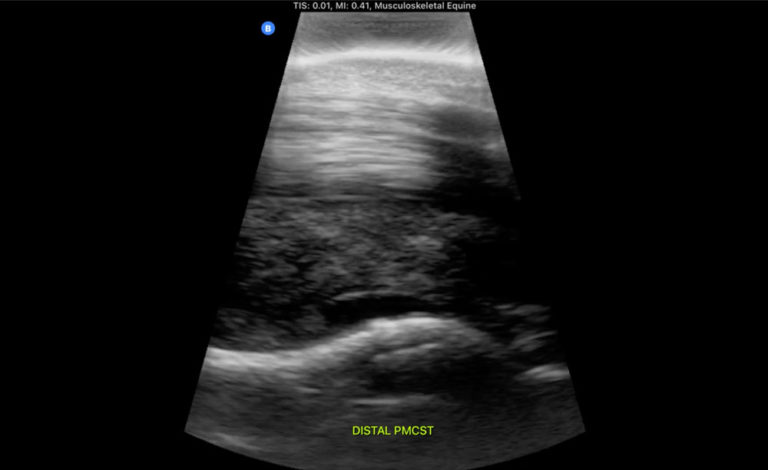

ultrasound horse PMCST

Butterfly Equine Ultrasound Tips: Dynamic Functional Ultrasound Imaging